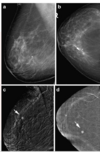

What pathology does this depict? [1]

Placenta praevia Fig 3 – Anterior placenta previa. The placenta (arrow) has covered the internal os completely (arrowhead).